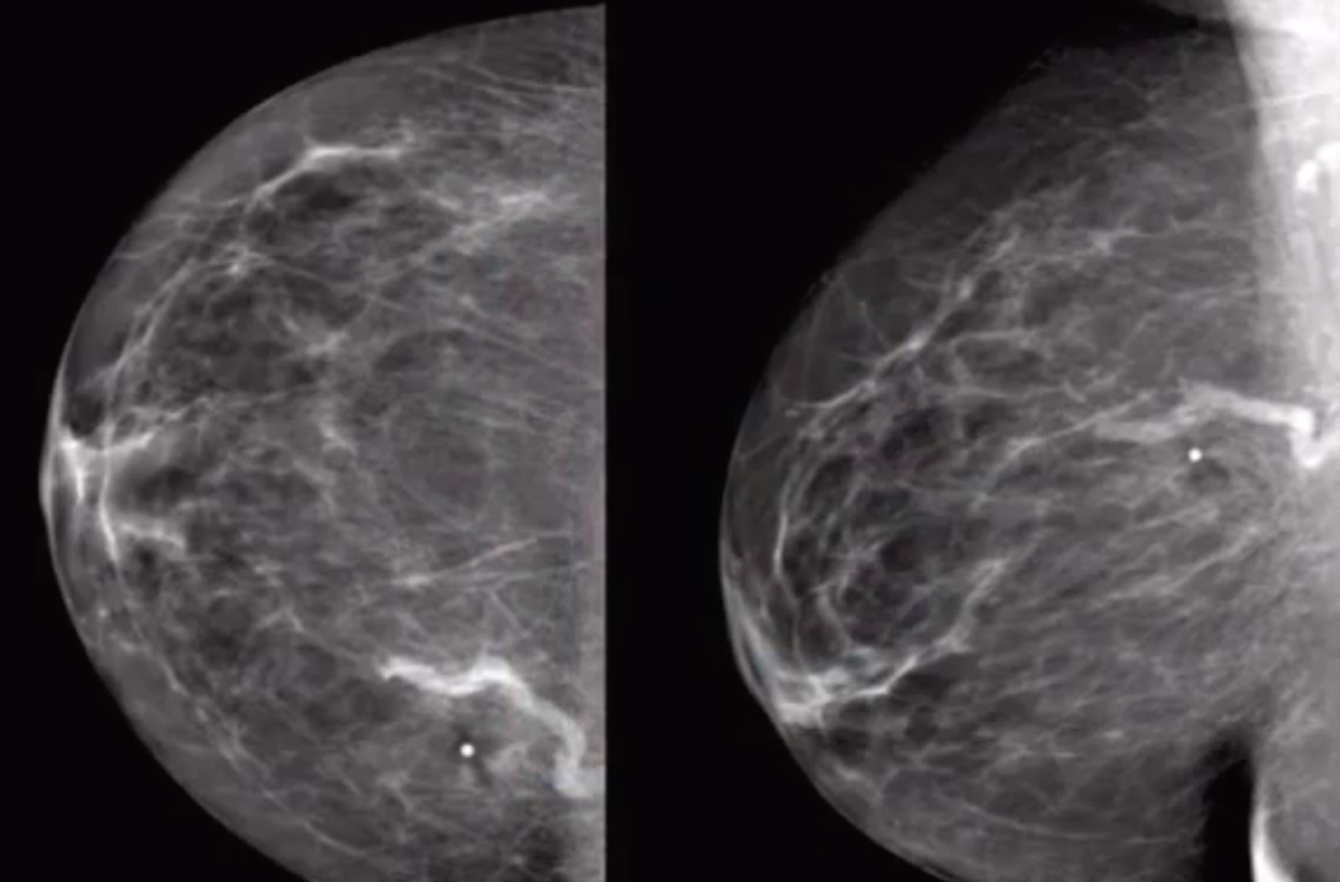

Fibroadenoma

• Round well circumscribed mass with central scar

• Largely hypoechoic with hyper-echoic central scar

• Mass in pre-menopausal woman (estrogen dependent)

• If seen in an older person it will have bulky popcorn calcs, with increased calcs in it over time